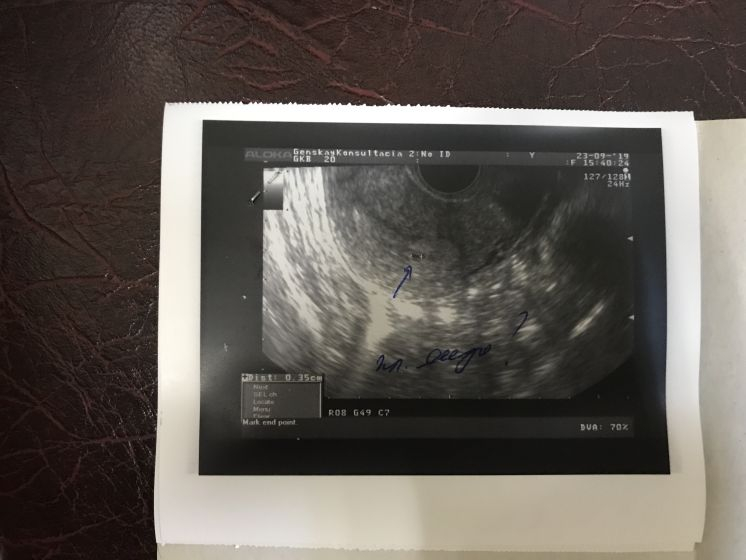

Результаты: УЗИ, КТГ, доплера, скринингаВрач направила на узи, сказали все норм, но я смотрю у девочек и на раннем сроке уже пишут ктр, а у меня не визуализируется(( Когда его видно станет? Переживаю

вы просто рано пошли) при таких размерах ничего не разглядеть. главное что беременность маточная, теперь растите)

Не переживайте, плодное яйцо еще очень маленькое, в нем невозможно ничего разглядеть) Недель в 7 акушерских уже можно идти смотреть ктр и сердцебиение)

так вы наверно рано ) чтобы мерить ктр 6адо увидеть эмбрион ...

у меня его в 6 нашли и то 1 мм